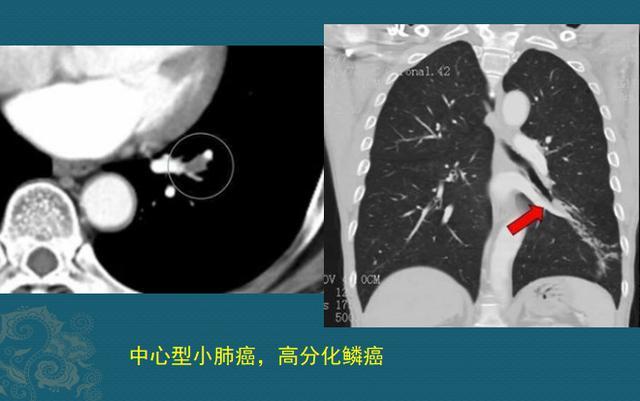

病例2,高难度的手术

这是一位64岁男病人,老烟民,牙齿都是焦黄的,反复咳嗽、痰多40天,胸闷10天,CT发现左侧中心型肺癌:

图片

下面的图是手术后3.5年复查,左肺全切,没有复发

中心型肺癌手术要慎重,需要术前充分评估,除了排查有无远处转移之外,还要重点观察对肺门血管、气管的侵袭范围,判断有无手术条件。

随着胸外科各种微创技术的进步,很多禁区也在不断突破!豪大夫最佩服的就是胸外科医生,因为肺癌发病率最高,而每一个小突破都能给成千上万的病带来新希望!这位病人做了左侧全肺切除,昨天回来复查,已经3年半了,没有复发。